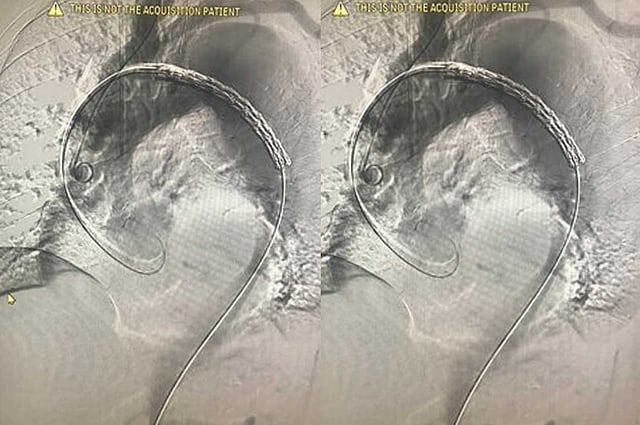

وذكر بيانٌ صادرٌ عن المستشفى، اطلعت عليه «عاجل»، اليوم الأحد، أنّ فريقًا طبيًا بقسم جراحة الأوعية الدموية التداخلية، أجرى عملية أوعية دموية تداخلية (قسطرة) لحاج باكستاني يبلغ من العمر 70 عامًا، يعاني انسلاخًا بالشريان الأورطي، ممتدًا من الصدر إلى الشريان الفخذي.

وأضاف البيان، أنّه تم وضع دعامتين خلال العملية، التي استغرقت ثلاث ساعات وتكلّلت بالنجاح.